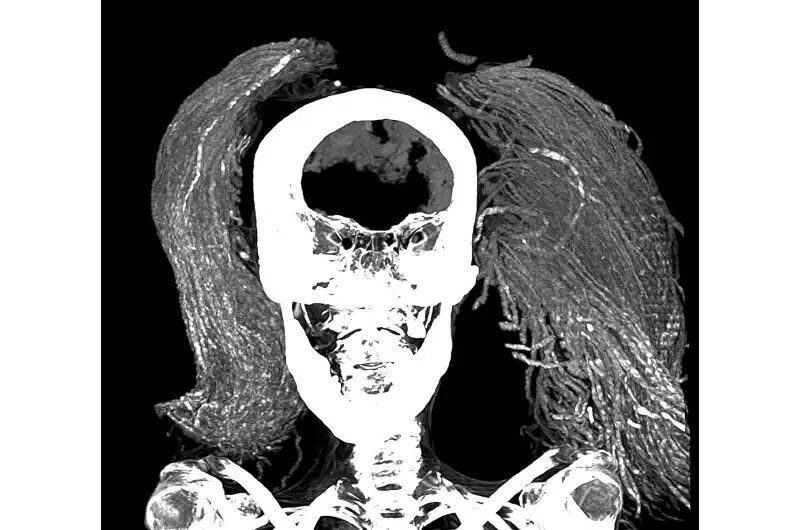

در پژوهش اخیر، سلیم از سی‌تی‌اسکن برای تشریح مجازی مومیایی و تخمین سن او، شناسایی آسیب‌شناسی‌ها و وضعیت نگهداری او استفاده کرد. او و همکارش دکتر سامیه المرقانی از فن‌های پیشرفته‌ای مانند میکروسکوپ الکترونی روبشی (SEM)، طیف‌سنجی تبدیل فوریه فروسرخ (FTIR) و آنالیز پراش اشعه ایکس (XRD) برای شناسایی مواد استفاده کردند.

سلیم از تصاویر CT دوبعدی و سه‌بعدی تخمین زد که قد زن در زمان زندگی ۱.۵۴ متر بوده است. بر اساس مورفولوژی مفصل بین دو استخوان لگن، که با افزایش سن صاف می‌شود، تصاویر سی تی تخمین زدند که او در زمان مرگ تقریباً ۴۸ سال سن داشته است. او از آرتریت خفیف ستون فقرات رنج می‌برد که از وجود استئوفیت‌ها یا خار‌های استخوانی روی مهره‌ها مشهود بود.

همچنین هیچ برشی بر بدن مومیایی پیدا نشد و این بااینکه مغز، دیافراگم، قلب، ریه‌ها، کبد، طحال، کلیه‌ها و روده هنوز وجود دارند، مطابقت داشت. این تعجب‌آور بود، زیرا روش کلاسیک مومیایی در پادشاهی جدید (۱۵۵۰-۱۰۶۹ قبل از میلاد) شامل برداشتن همه این اندام‌ها به‌جز قلب بود.